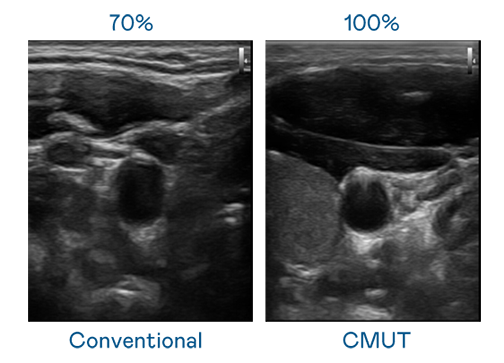

CMUT 技术是一种用电容式微机电元件来产生超音波讯号的技术。与传统 PZT 压电式技术相比,CMUT 频宽增加 30%,更宽频的超音波讯号让影像解析度大幅提升,是实现高影像品质医疗超音波扫描、促进精准医疗发展的关键技术。

超音波影像的解析度高低,首先取决于探头能发出的讯号频宽。九游会ag CMUT 可提供高清晰的超音波讯号,提供高频宽、高灵敏度、影像纹理细节更高的超音波影像,协助医护人员缩短影像判读时间及利用精准的医疗影像进行诊断。